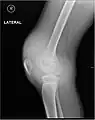

Radiographie montrant les complications liées à l'hémarthrose. Radiographie montrant les complications liées à l'hémarthrose.